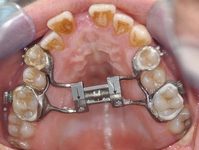

Çeneyi Nasıl İleri Alabilirim?Çene yapısı, yüz estetiği ve fonksiyonu açısından önemli bir rol oynamaktadır. Çenenin ileri ya da geri pozisyonu, yüz simetrisi, diş sağlığı ve genel estetik algı üzerinde belirleyici etkilere sahiptir. Bu makalede, çenenin nasıl ileri alınabileceği üzerine çeşitli yöntemler ve teknikler ele alınacaktır. 1. Ortodontik Tedavi YöntemleriOrtodontik tedavi, dişlerin ve çenenin düzgün bir şekilde hizalanmasını sağlamak amacıyla kullanılan bir yöntemdir. Çenenin ileri alınmasında aşağıdaki ortodontik yaklaşımlar etkili olabilir: